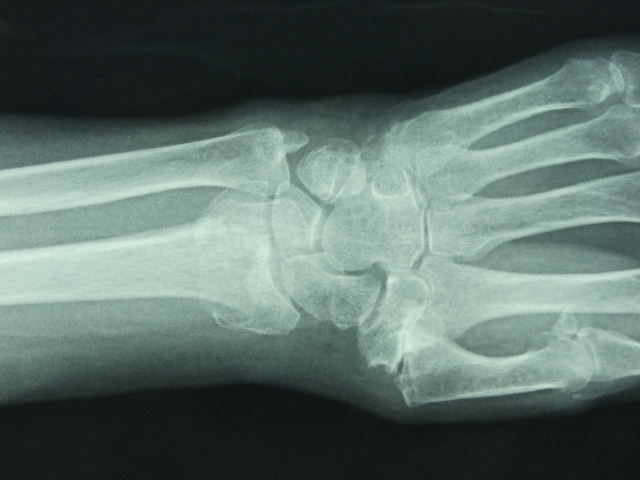

ACT Alteraciones degenerativas en muñeca.